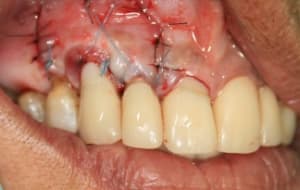

greffe_43-44__montage-1__ylawrg.jpg